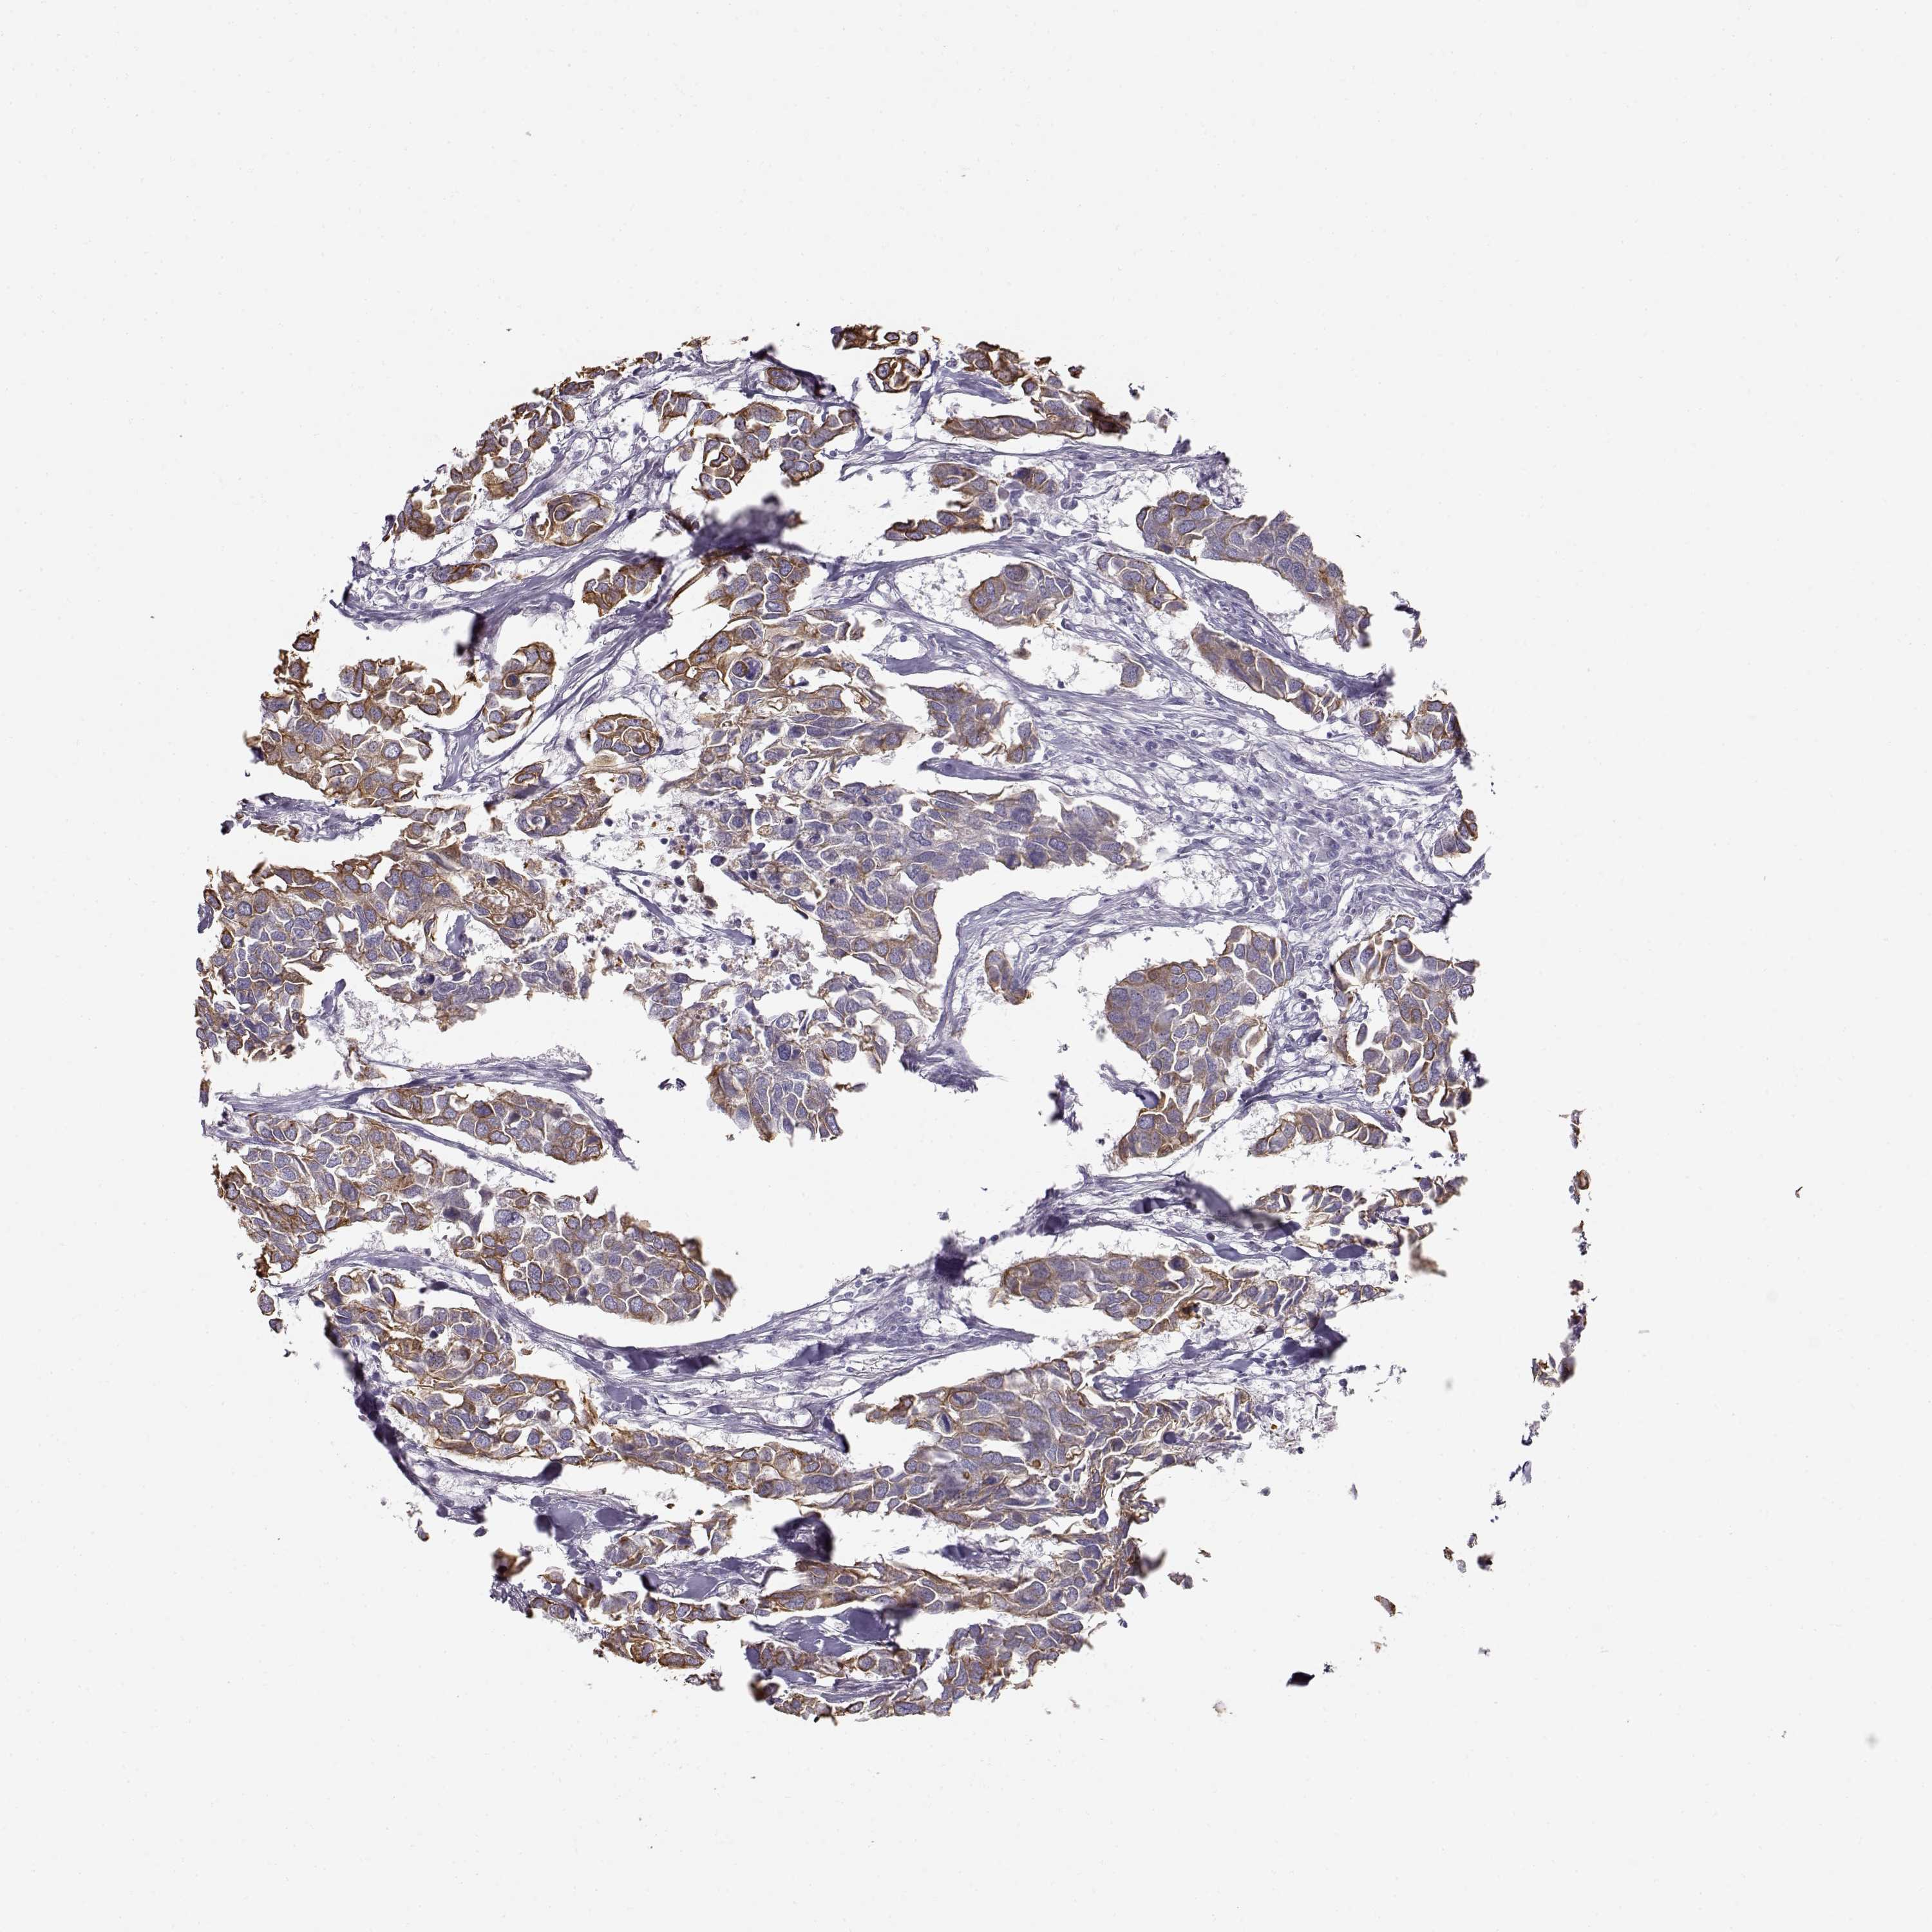

CANCER BREAST CANCER Show tissue menu

BRCA TCGA BRCA VALIDATION PROTEIN EXPRESSION